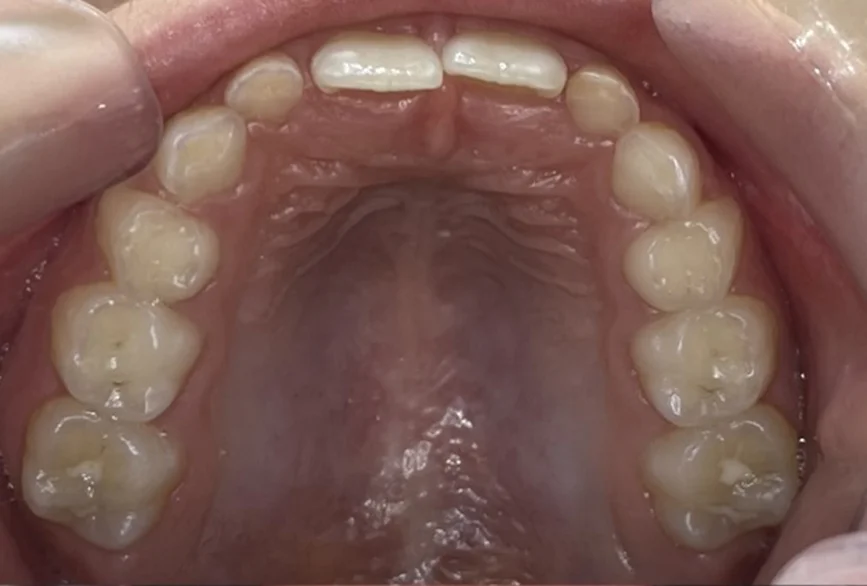

Клинични резултати:

Хармонични зъби дъги с достатъчно място за пробива на постоянните зъби.

Осигуряване на възможност за правилен растеж и съотношение на двете челюсти.

Коригирана е кръстосаната захапка и при усмивка вече се виждат горните фронтални зъби.